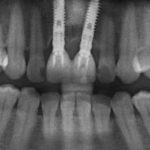

Несколько лет назад пациенту установили три имплантата, но протезировать их не смогли. Два из трех установленных имплантов благополучно выпали, один остался. Но даже по этому одному имплантату понятно, почему нормальное протезирование в его случае было просто невозможно (на фото).

Несколько лет назад пациенту установили три имплантата, но протезировать их не смогли. Два из трех установленных имплантов благополучно выпали, один остался. Но даже по этому одному имплантату понятно, почему нормальное протезирование в его случае было просто невозможно (на фото).

Причём, вроде как, к имплантологу претензий не предъявить (к слову, это был один известный профессор), ибо «имплант интегрировался, всё в порядке, а то, что протезировать не могут, так это … ортопед-мудак«. Хотя, я уверен, вы понимаете, в чём причина, по которой здесь ничего нельзя сделать, кроме удаления импланта.